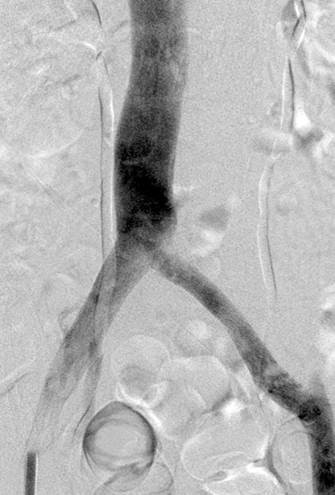

Vista de posición decúbito prono de trombo agudo en la vena femoral común izquierda y ausencia de flujo en las venas ilíacas.